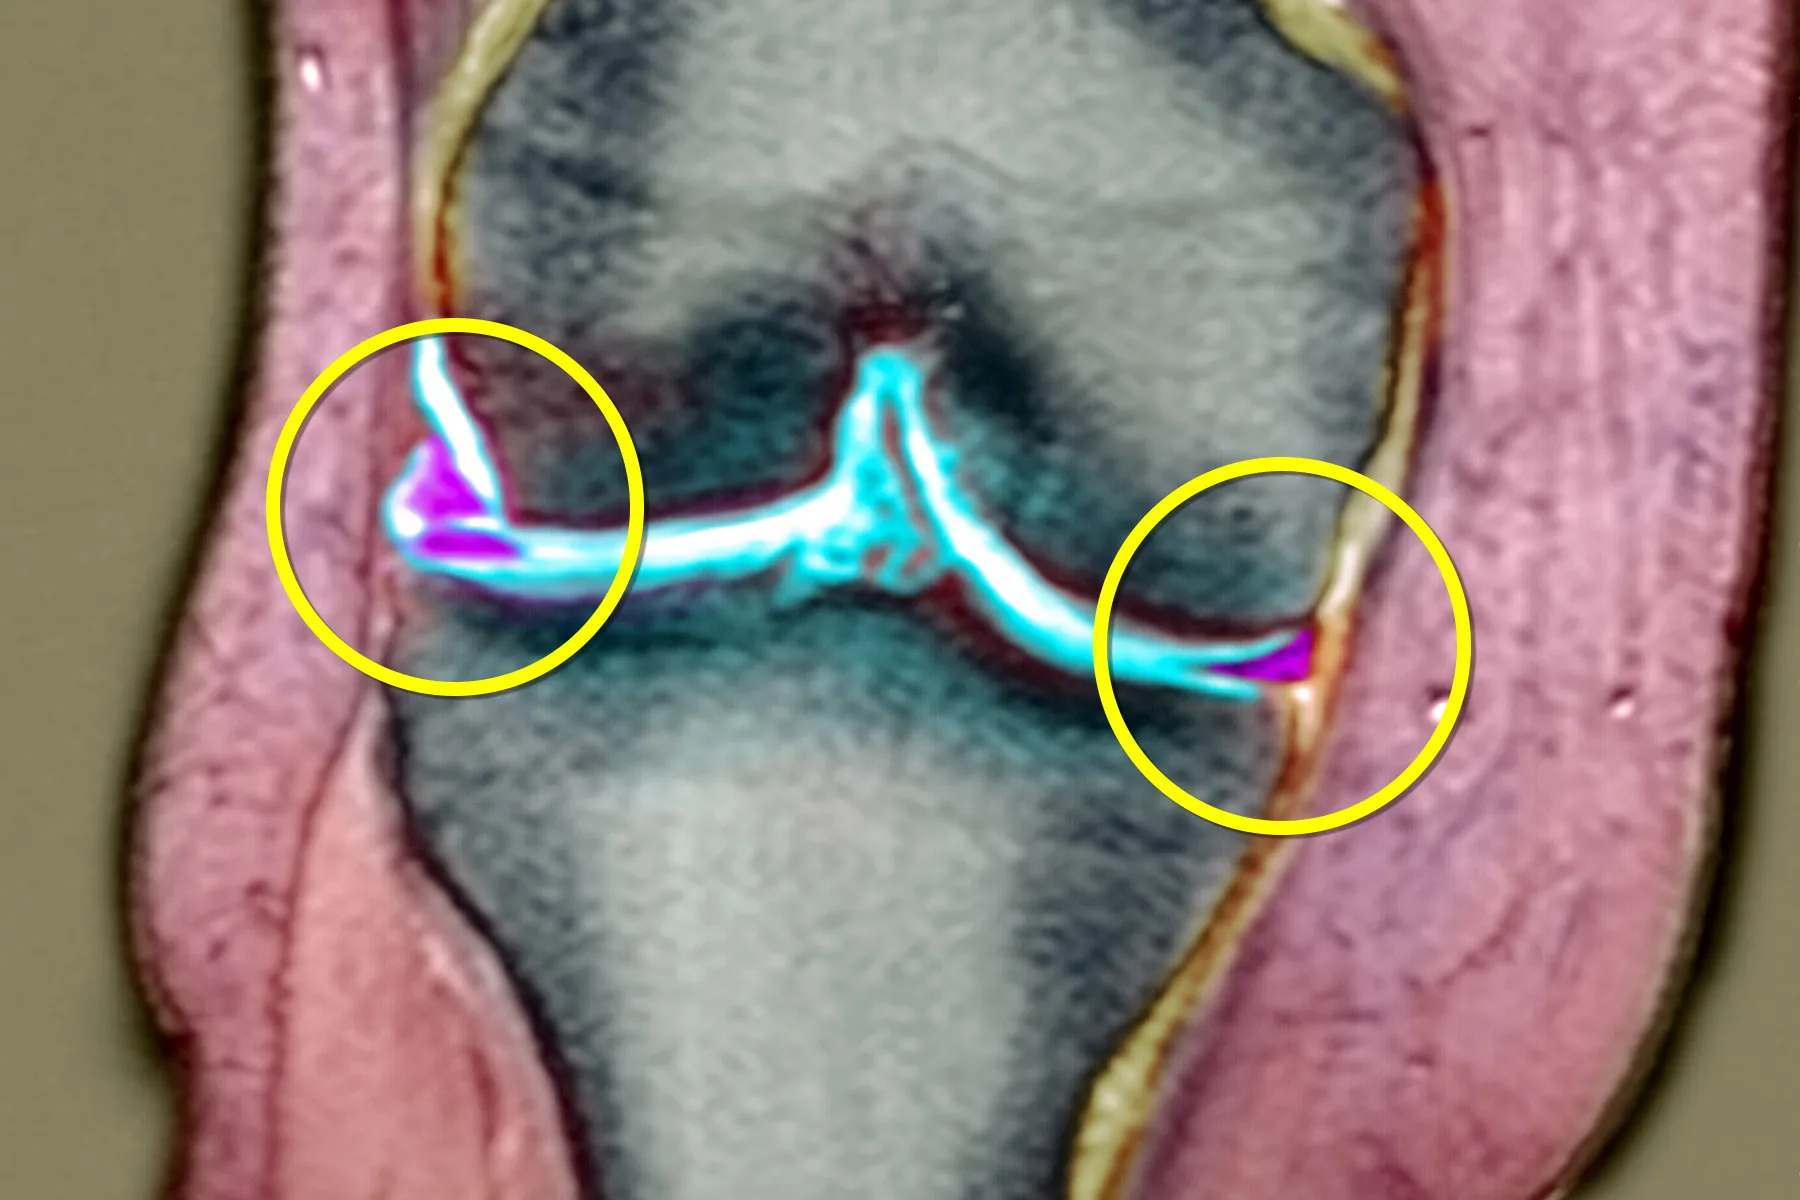

عکس پارگی مینیسک زانو و روشهای تشخیصی

برای تشخیص دقیق پارگی مینیسک، پزشکان از روشهای تصویربرداری استفاده میکنند. مهمترین ابزارها عبارتند از:

MRI (تصویربرداری رزونانس مغناطیسی): دقیقترین روش برای مشاهده پارگی مینیسک و میزان آسیبدیدگی.

عکسهای MRI میتوانند به وضوح نشان دهند که پارگی در چه بخشی از مینیسک رخ داده و آیا نیاز به جراحی یا درمان غیرجراحی وجود دارد.